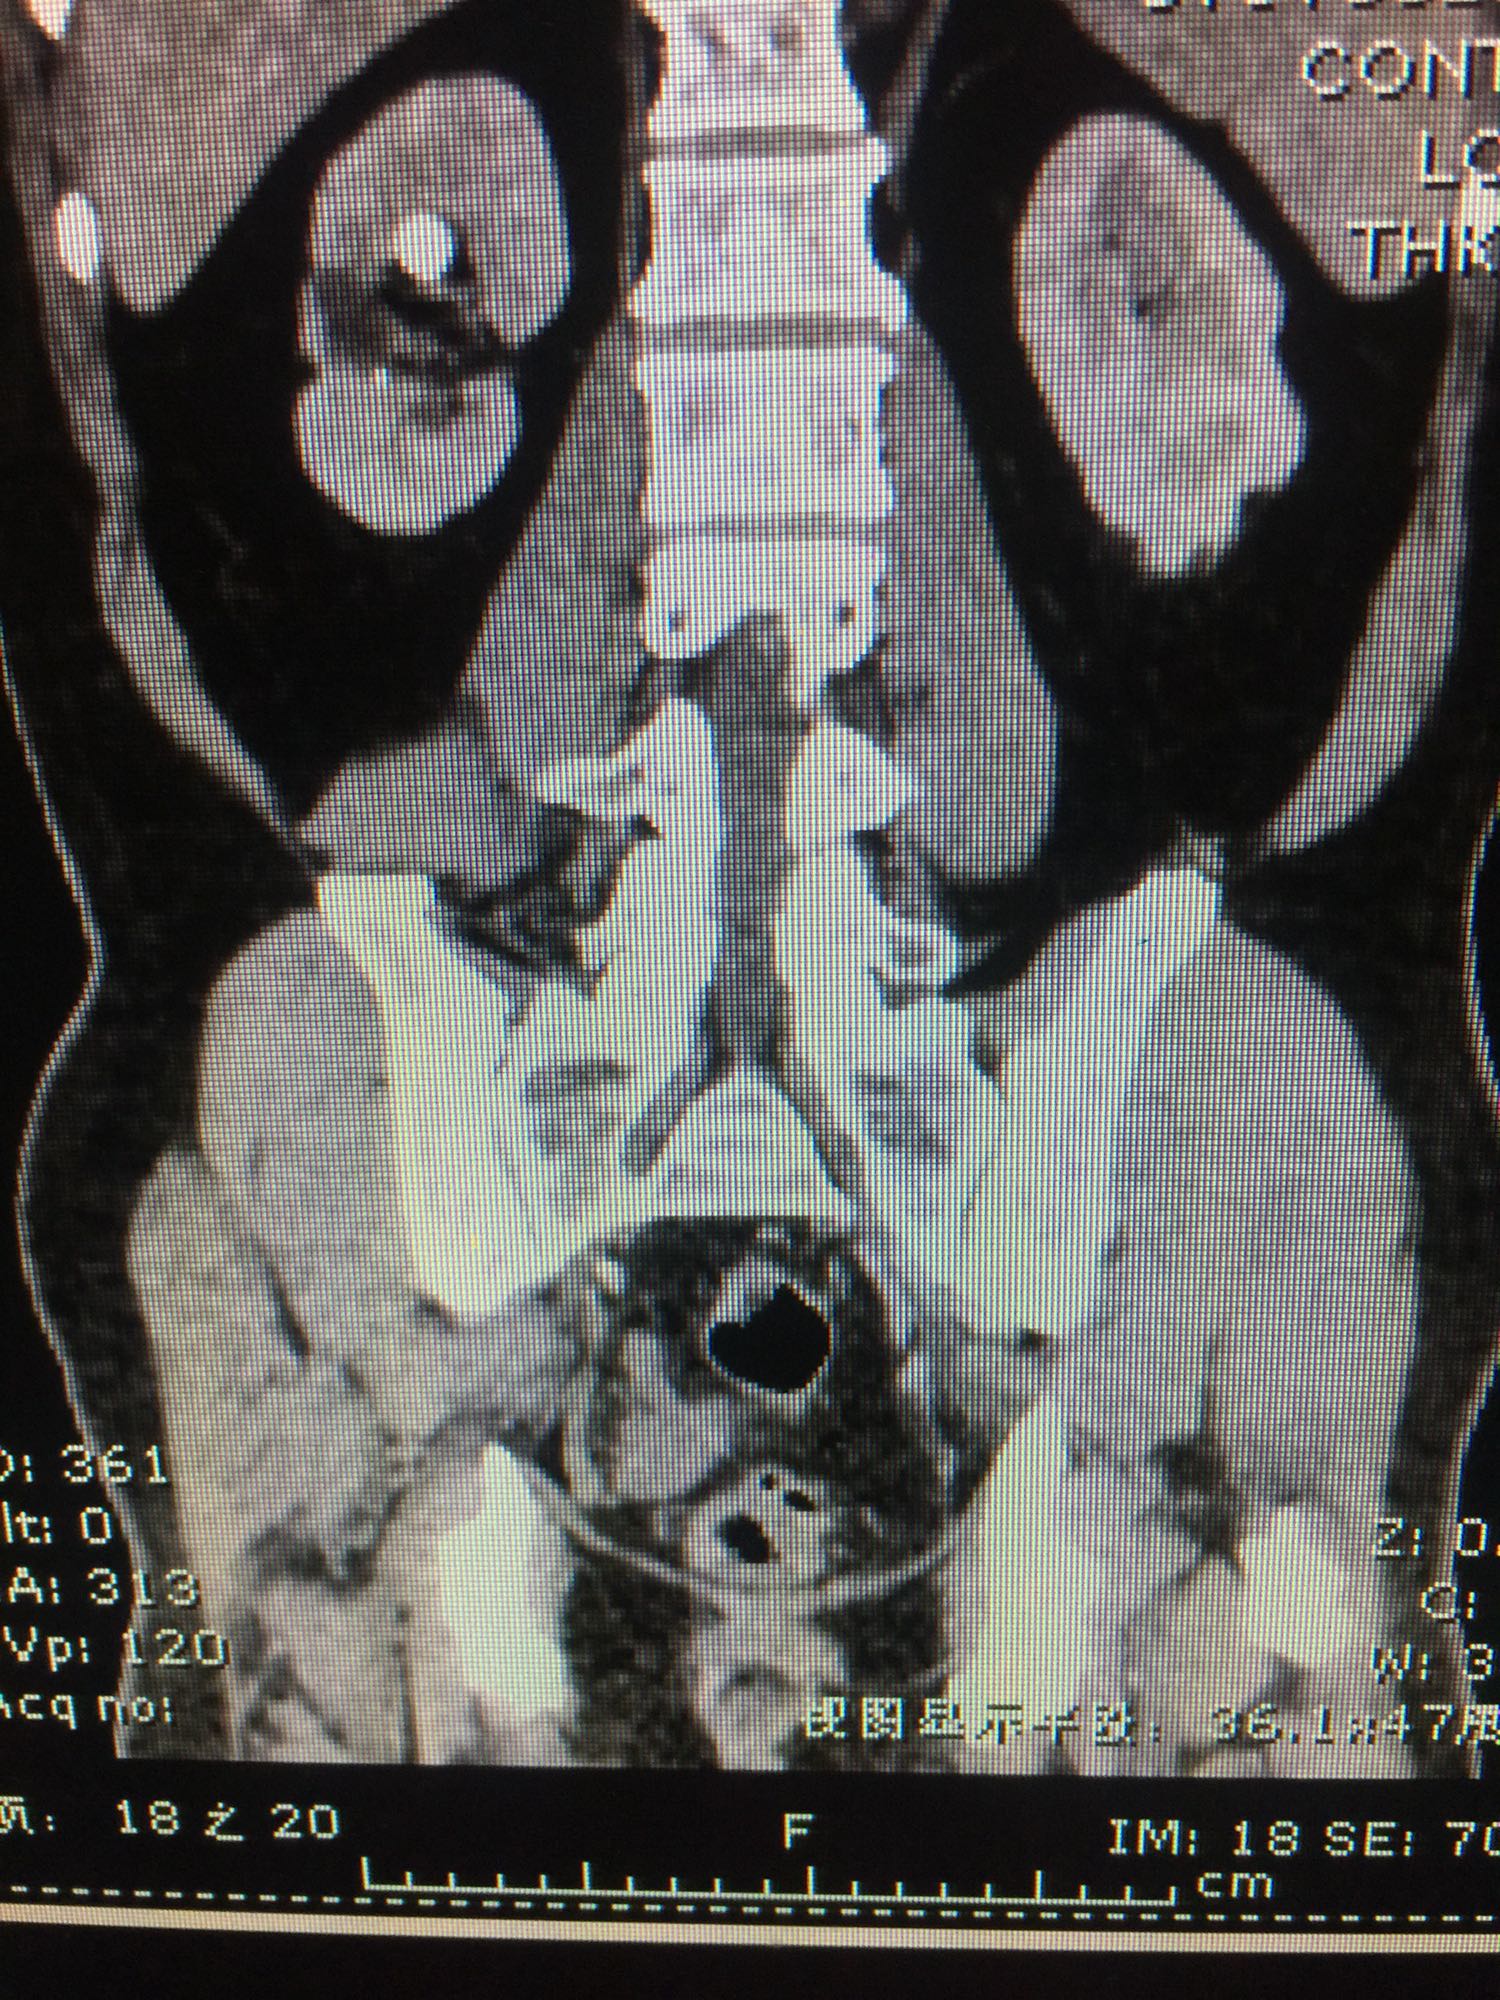

60岁男性 既往无高血压糖尿病等病史 检查发现右侧肾结石10年 10年前检查发现右侧肾结石,直径约1厘米,未给予正规治疗,近日来我院门诊,行彩超发现右肾多发结石,进一步治疗入院。

查体:双肾区无叩压痛,膀胱区无叩压痛,无叩浊,前列腺二度,质地中等,无压痛,无结节。CTU提示右肾铸型结石。ECTL 40,R14.5

右肾铸型结石 予以经皮肾碎石治疗,术后复查平片未见结石残留。